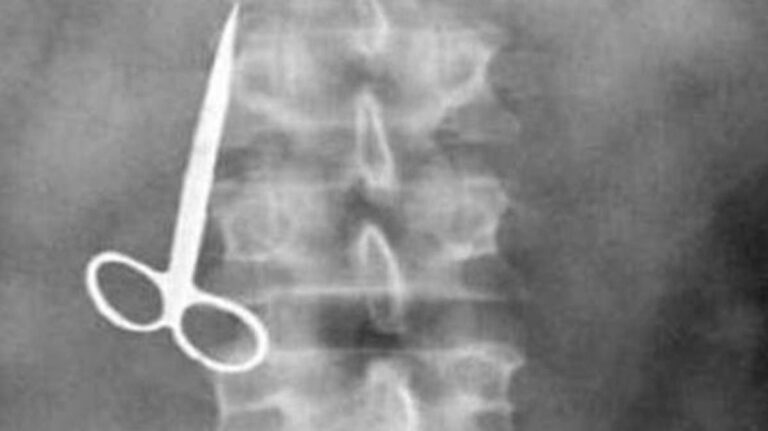

في مشهد متكرر و مألوف للعيان، تم استخراج مقص، بقي في بطن امرأة لمدة عقدين. المرأة “باتشينا خاتون”. عانت من آلام طوال هذه المدة لكن لم يخيل لها ولو لحظة أن إهمالا طبيا أثناء عملية جراحية سابقة، سيكون سببا في أوجاعها.

ووفقا لما نقلته صحيفة “لاراثون” الإسبانية، نجح فريق طبي بنجلاديشي هذا الأسبوع في إزالة مقص جراحي بقي 20 عامًا في بطن المرأة.

ونقلا عن الأطباء، أوضحت “وطن” حسب ما ترجمته، أن المريضة خضعت لعملية جراحية في عيادة طبية في عام 2002 لإزالة حجر من المرارة. و “بطريقة ما، بقي المقص في الداخل بعد إنهاء العملية والإجراءات المترتبة عن ذلك”.

وقال الطبيب “عندما أتت إلينا مؤخرًا طلبنا أشعة سينية كشفت أخيرًا عن وجود مقص داخل بطنها”. وأكد أن المريضة بصدد التعافي الآن وهي بخير.